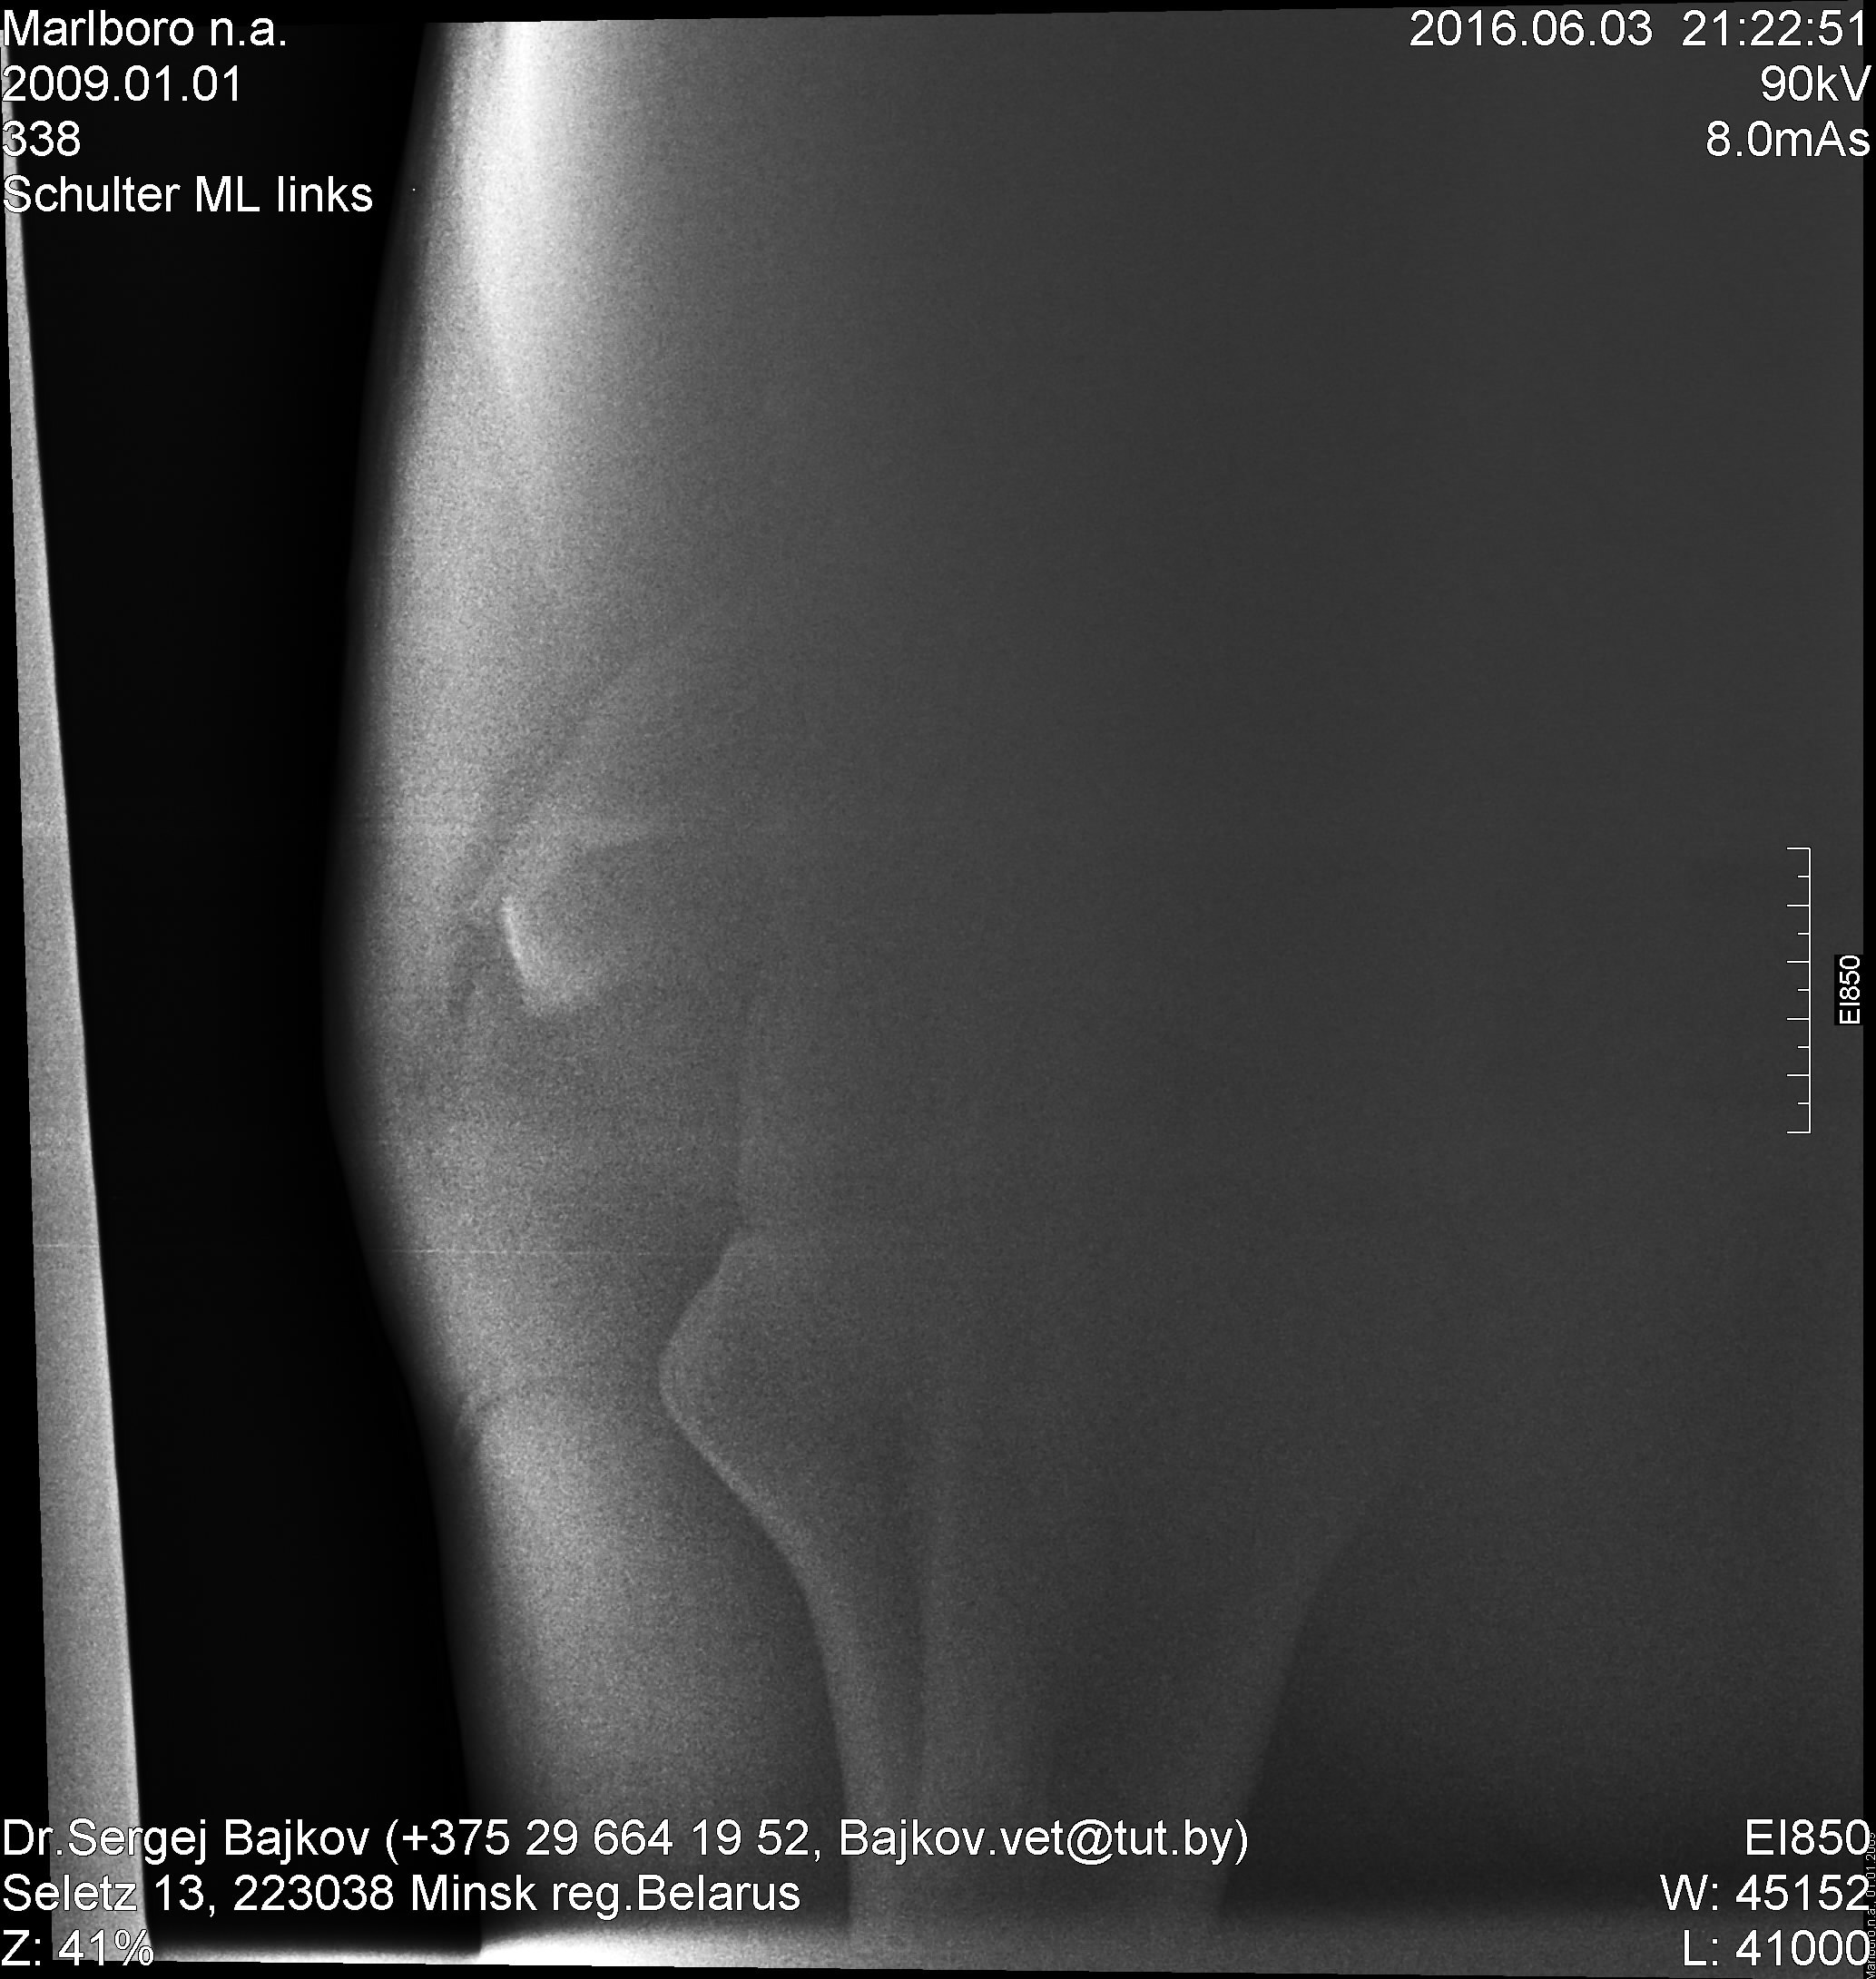

Собственно, еще до первого рентгена его смотрела наш врач. И потом всю дорогу готовила меня морально "надо делать снимок, но диагноз неблагополучный". После снимка, другой уже врач -- цитирую -- "п...ц. Кость в хлам".

И тоже однозначно -- усыплять.

Ночь никто не спал, все думали, какие могут быть варианты. Той ночью я придумала конструкцию, как перевезти лошадь с такой травмой, например, в московскую клинику. Отослала снимки кому только можно.

И -- нам не отказали. Запросили дополнительные снимки. Анатомические атласы. Кость с анатомички.